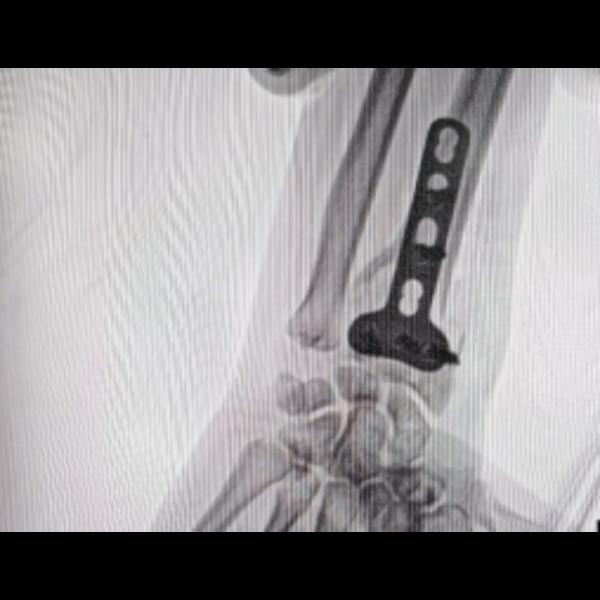

Treated with curettage with electrical burr and fixation with bone cement and lower end radius plate...

Giant cell tumour of lower end radius with Pathological fracture !